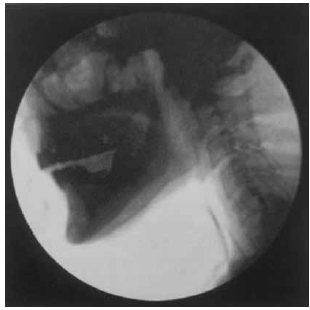

A Videofluoroscopia da Deglutição (VFD) possibilita a avaliação completa e dinâmica de todas as fases da deglutição, bem como apresenta grande sensibilidade e especificidade na detecção de aspiração. Observe a figura a seguir.

(Magalhães e Magnoni: Disfagia orofaríngea no adulto em ambiente hospitalar. Rubio, 2022. p. 81)

Assinale a alternativa que apresenta uma descrição compatível com o exame apresentado.